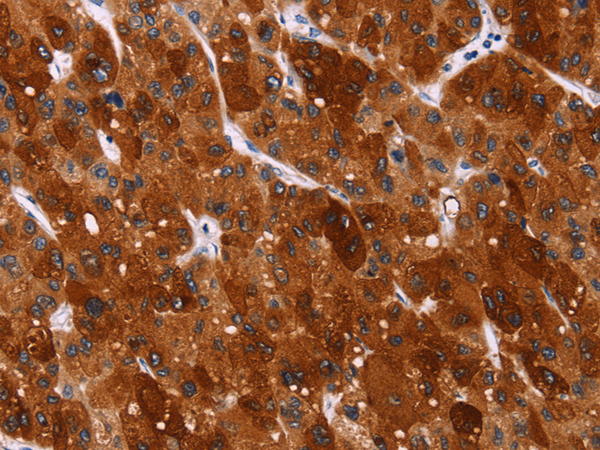

分类: 科研抗体货号: P11837别名: GIG8; ID2A; ID2H; bHLHb26应用: IHC反应种属: Human, Mouse, Rat